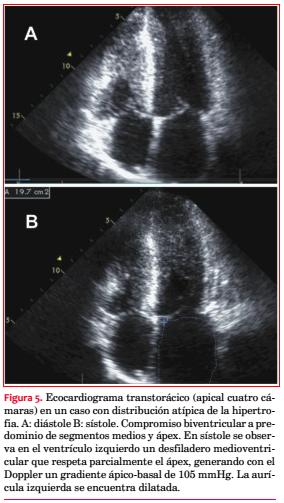

Se observó una paciente de 16 años muy sintomática, con máxima hipertrofia septal media y de ápex y severa estenosis medioventricular, con participación similar del ventrículo derecho (VD) (figura 5). Los demás pacientes presentaron la obstrucción en el TSVI.

Debemos señalar que en nuestra serie solo se practicaron maniobras sensibilizadoras durante el estudio ecocardiográfico en la cuarta parte de ellos. Solamente en un caso la obstrucción no asentó a nivel del TSVI sino medio ventricular, variante reputada como rara(89-91), que no obstante ocurre hasta en 9,4% en ciertas series(92), y se asocia con mayor discapacidad, disfunción ventricular, ACV y mortalidad súbita y por IC(92,93).